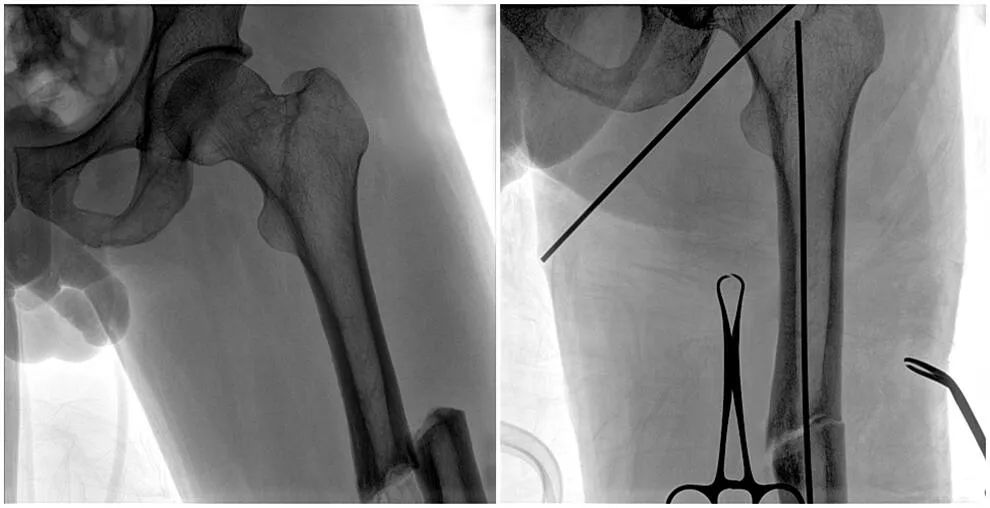

C形臂輔助手術過程

術中使用普愛醫(yī)療大平板一體式C形臂進行透視,判斷骨折情況及克氏針、髓內釘?shù)冉饘僦踩胛锏奈恢?,進行調整。C形臂準確的術中定位,大大縮短了手術的時間,減輕了患者的痛苦,輔助手術順利完成。

在進行髓內釘內固定術時,醫(yī)生需要同時觀察到入釘點和骨折部位的情況,普愛醫(yī)療大平板一體式C形臂采用30CM×30CM的平板探測器,能夠呈現(xiàn)更廣闊的成像面積,滿足大部分長骨髓內釘內固定術的攝片需求。

術中定位準確、出血量少,術后影像顯示股骨移位糾正,恢復良好力線,手術效果良好。